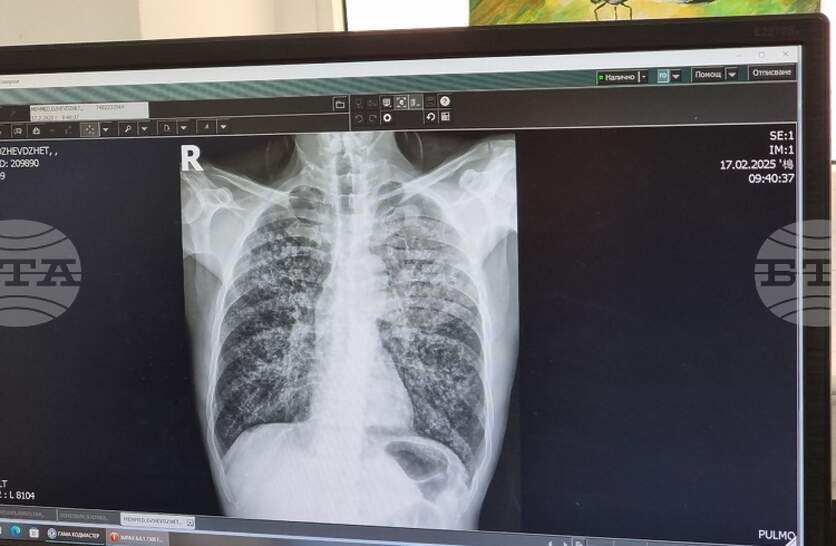

Ранна и бърза диагностика, скрининг сред уязвими групи, навременно лечение, обучения на медици, повишена осведоменост сред населението се предвиждат в проекта на Национална програма за превенция на туберкулозата в Република България 2026-2030 г. Проектът е публикуван на сайта на Министерството на здравеопазването за едномесечно обществено обсъждане. Във финансовия план към проекта на програмата са предвидени 4 440 100 млн. евро, които ще бъдат осигурени от бюджета на МЗ. В България, след 1998 г., се наблюдава трайна тенденция на намаляване на заболеваемостта от туберкулоза - от 49,9 заболели на 100 000 население през 1998 г. до 13,7 заболели на 100 000 през 2024 г. Данните на Световната здравна организация през 2024 г. показват, че приблизително 10,7 млн. души в света са диагностицирани с туберкулоза, от които 5,8 млн. са мъже, 3,7 млн. - жени и 1,2 млн. - деца. Туберкулозата е тежко инфекциозно заболяване, което засяга най-често белите дробове, но също така и други органи на човешкото тяло, като се смята, че около една четвърт от хората в света са носители на микробактерии, причиняващи туберкулоза (латентна туберкулоза). Тези хора са асимптоматични и не са заразни за околните, но средно около 10% от тях развиват активна туберкулоза. Симптомите на белодробната туберкулоза са кашлица с храчки (понякога с кръв), болка в гърдите, задух и общо усещане за слабост. Извънбелодробната туберкулоза може да засегне всяка част на тялото, като най-честата локализация са ставите и костите. Основните рискови фактори за развитие на туберкулоза са: употребата на алкохол, тютюнопушене, имуносупресия и недохранване. Риск от развитие на туберкулоза има и за хора, засегнати от ХИВ, от диабет, рак или приемащи имуносупресивни лекарства заради химиотерапия, трансплантация, ревматоиден артрит, псориазис или болест на Крон и др. В риск могат да бъдат деца, възрастни хора, лица, идващи от страни с висока честота на заболяването или живеещи в пренаселени пространства, при лоши битови условия, употребяващи с наркотици. Огромните щети, причинени от заболяването в личен и обществен план, както и значителните разходи за изграждане и функциониране на система за откриване на случаите, диагностика и лечение, налагат необходимостта от предприемане на действия за ограничаване на разпространението му. МЗ провежда дългогодишна политика по превенция на туберкулозата чрез приемане и изпълнение на национални програми в четири програмни периода - 2007-2011 г., 2012-2015 г., 2017-2020 г. и 2021-2025 г. Основните цели на програмите са намаляване на броя на заболелите и на починалите от туберкулоза, което е в съответствие с Целите за устойчиво развитие на ООН, Стратегията на СЗО за край на туберкулозата до 2035 г. и Плана за действие на Европейския регион на СЗО за намаляване на туберкулозата до 2030 г.